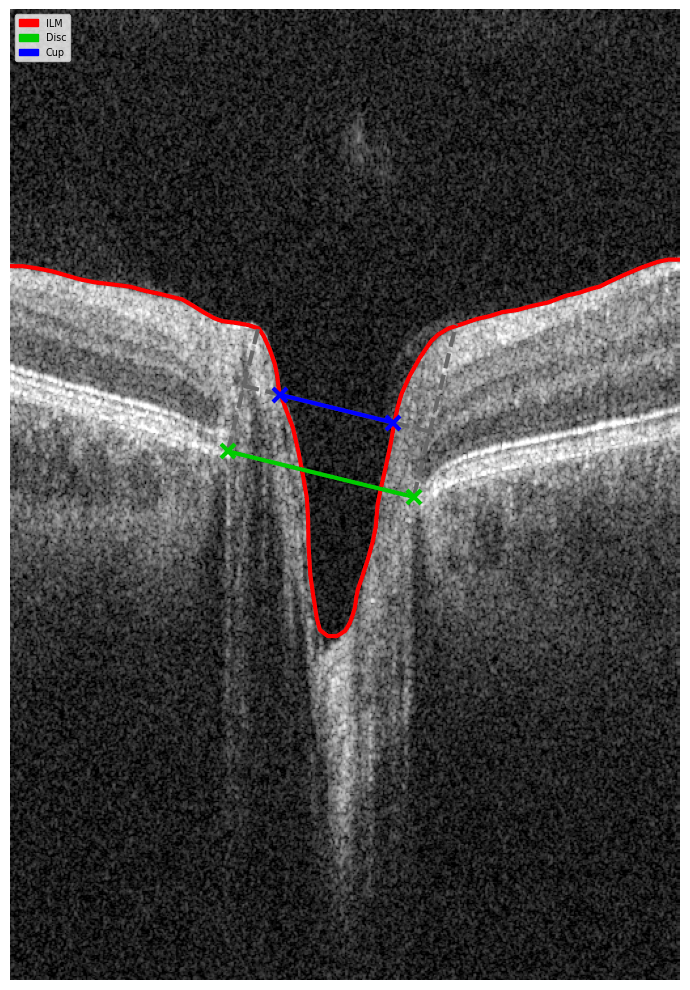

For instance, AI today can assess the early risk of glaucoma based on the GCC asymmetry measurements. Here is how AI-powered OCT workflow would look.

Millions risk irreversible vision loss due to undiagnosed glaucoma, underscoring the need for improved early detection. Current tests often rely on observing changes over time, delaying treatment assessment and hindering early identification of rapid disease progression. OCT frequently detects microscopic damage to ganglion cells and thinning across these layers before changes are noticeable through other tests. However, the earliest signs on the scan can still be invisible to the human eye.

AI algorithms offer insights into glaucoma detection by routinely analyzing the ganglion cell complex, measuring its thickness, and identifying any thinning or asymmetry to determine a patient’s glaucoma risk without additional clinician effort.

Another significant benefit of AI systems is that OCT for glaucoma usually utilizes a normative database to assess retinal normality. However, these databases are limited in size and represent an average of a select group of people, potentially missing early glaucoma development in those who deviate from the “norm.” Conversely, individuals may be unnecessarily referred for treatment due to not fitting the “normal” profile, even if their eyes are healthy.